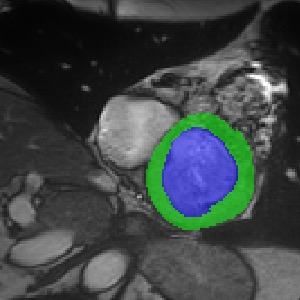

Transformers, the default model of choices in natural language processing, have drawn scant attention from the medical imaging community. Given the ability to exploit long-term dependencies, transformers are promising to help atypical convolutional neural networks (convnets) to overcome its inherent shortcomings of spatial inductive bias. However, most of recently proposed transformer-based segmentation approaches simply treated transformers as assisted modules to help encode global context into convolutional representations without investigating how to optimally combine self-attention (i.e., the core of transformers) with convolution. To address this issue, in this paper, we introduce nnFormer (i.e., Not-aNother transFormer), a powerful segmentation model with an interleaved architecture based on empirical combination of self-attention and convolution. In practice, nnFormer learns volumetric representations from 3D local volumes. Compared to the naive voxel-level self-attention implementation, such volume-based operations help to reduce the computational complexity by approximate 98% and 99.5% on Synapse and ACDC datasets, respectively. In comparison to prior-art network configurations, nnFormer achieves tremendous improvements over previous transformer-based methods on two commonly used datasets Synapse and ACDC. For instance, nnFormer outperforms Swin-UNet by over 7 percents on Synapse. Even when compared to nnUNet, currently the best performing fully-convolutional medical segmentation network, nnFormer still provides slightly better performance on Synapse and ACDC.